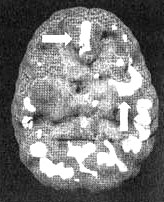

Мозг Стивена. Суицидальные мысли

Трехмерное изображение, вид снизу — активный мозг.

Трехмерное изображение, вид сбоку — активный мозг.

Обратите внимание на выраженно повышенную активность в левой височной доле и в поясной системе (стрелки).